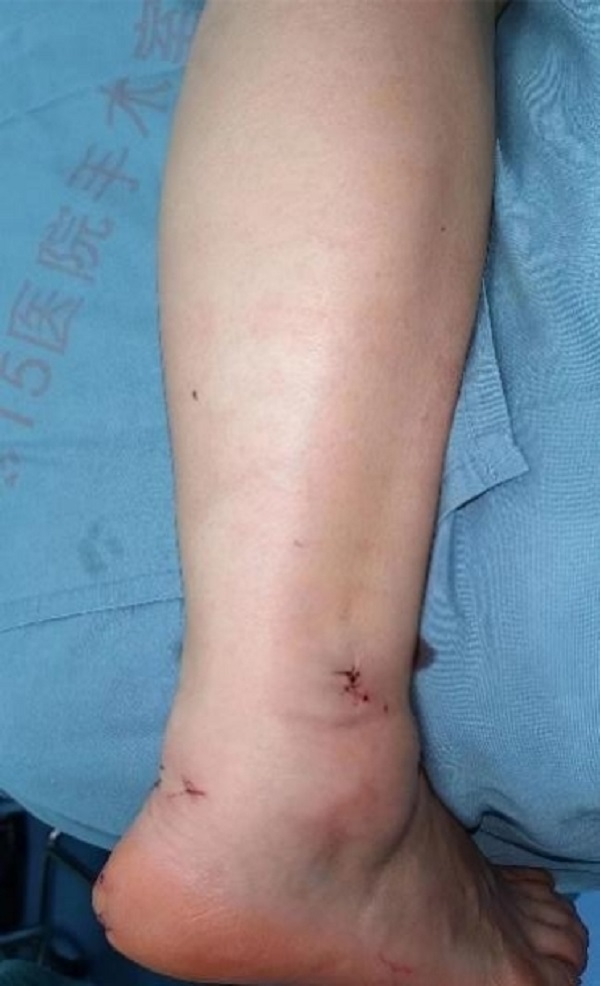

术后即刻外观照